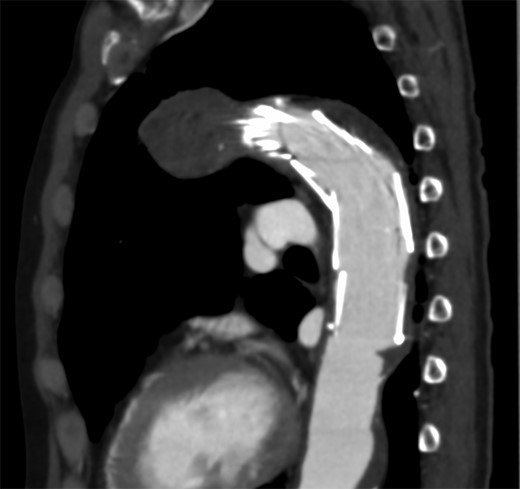

A 69-year-old male patient was admitted to our department with a diagnosis of three aortic aneurysms. His history included severe chronic obstructive pulmonary disease and hypertension. The aneurysms consisted of aortic arch saccular aneurysm with a protruding diameter of 25 mm, descending aortic aneurysm with a protruding diameter of 18 mm, and abdominal aortic aneurysm with a diameter of 36 mm. Of these, saccular aneurysm of the aortic arch required prompt treatment. We performed TEVAR using Najuta (Kawasumi, Tokyo, Japan) for this specific aneurysm and the operation was successful. After the operation, the patient complained of mild abdominal pain but on examination, there was no abdominal tenderness and the blood test showed no acidosis or abnormality. On the fourth post-operative day, patient suddenly complained of strong abdominal pain. Enhanced CT showed SMA embolism about 52 mm in length from the ileocolic artery bifurcation. As the distal side of the stent graft was placed to stick the thrombus of the aorta, it was thought that the embolus may have been liberated from this point (Fig. 1). We diagnosed SMA embolism and emergently performed revascularization with intervention radiology (IVR).

The distal side of the stent graft was placed to stick the thrombus of the aorta.